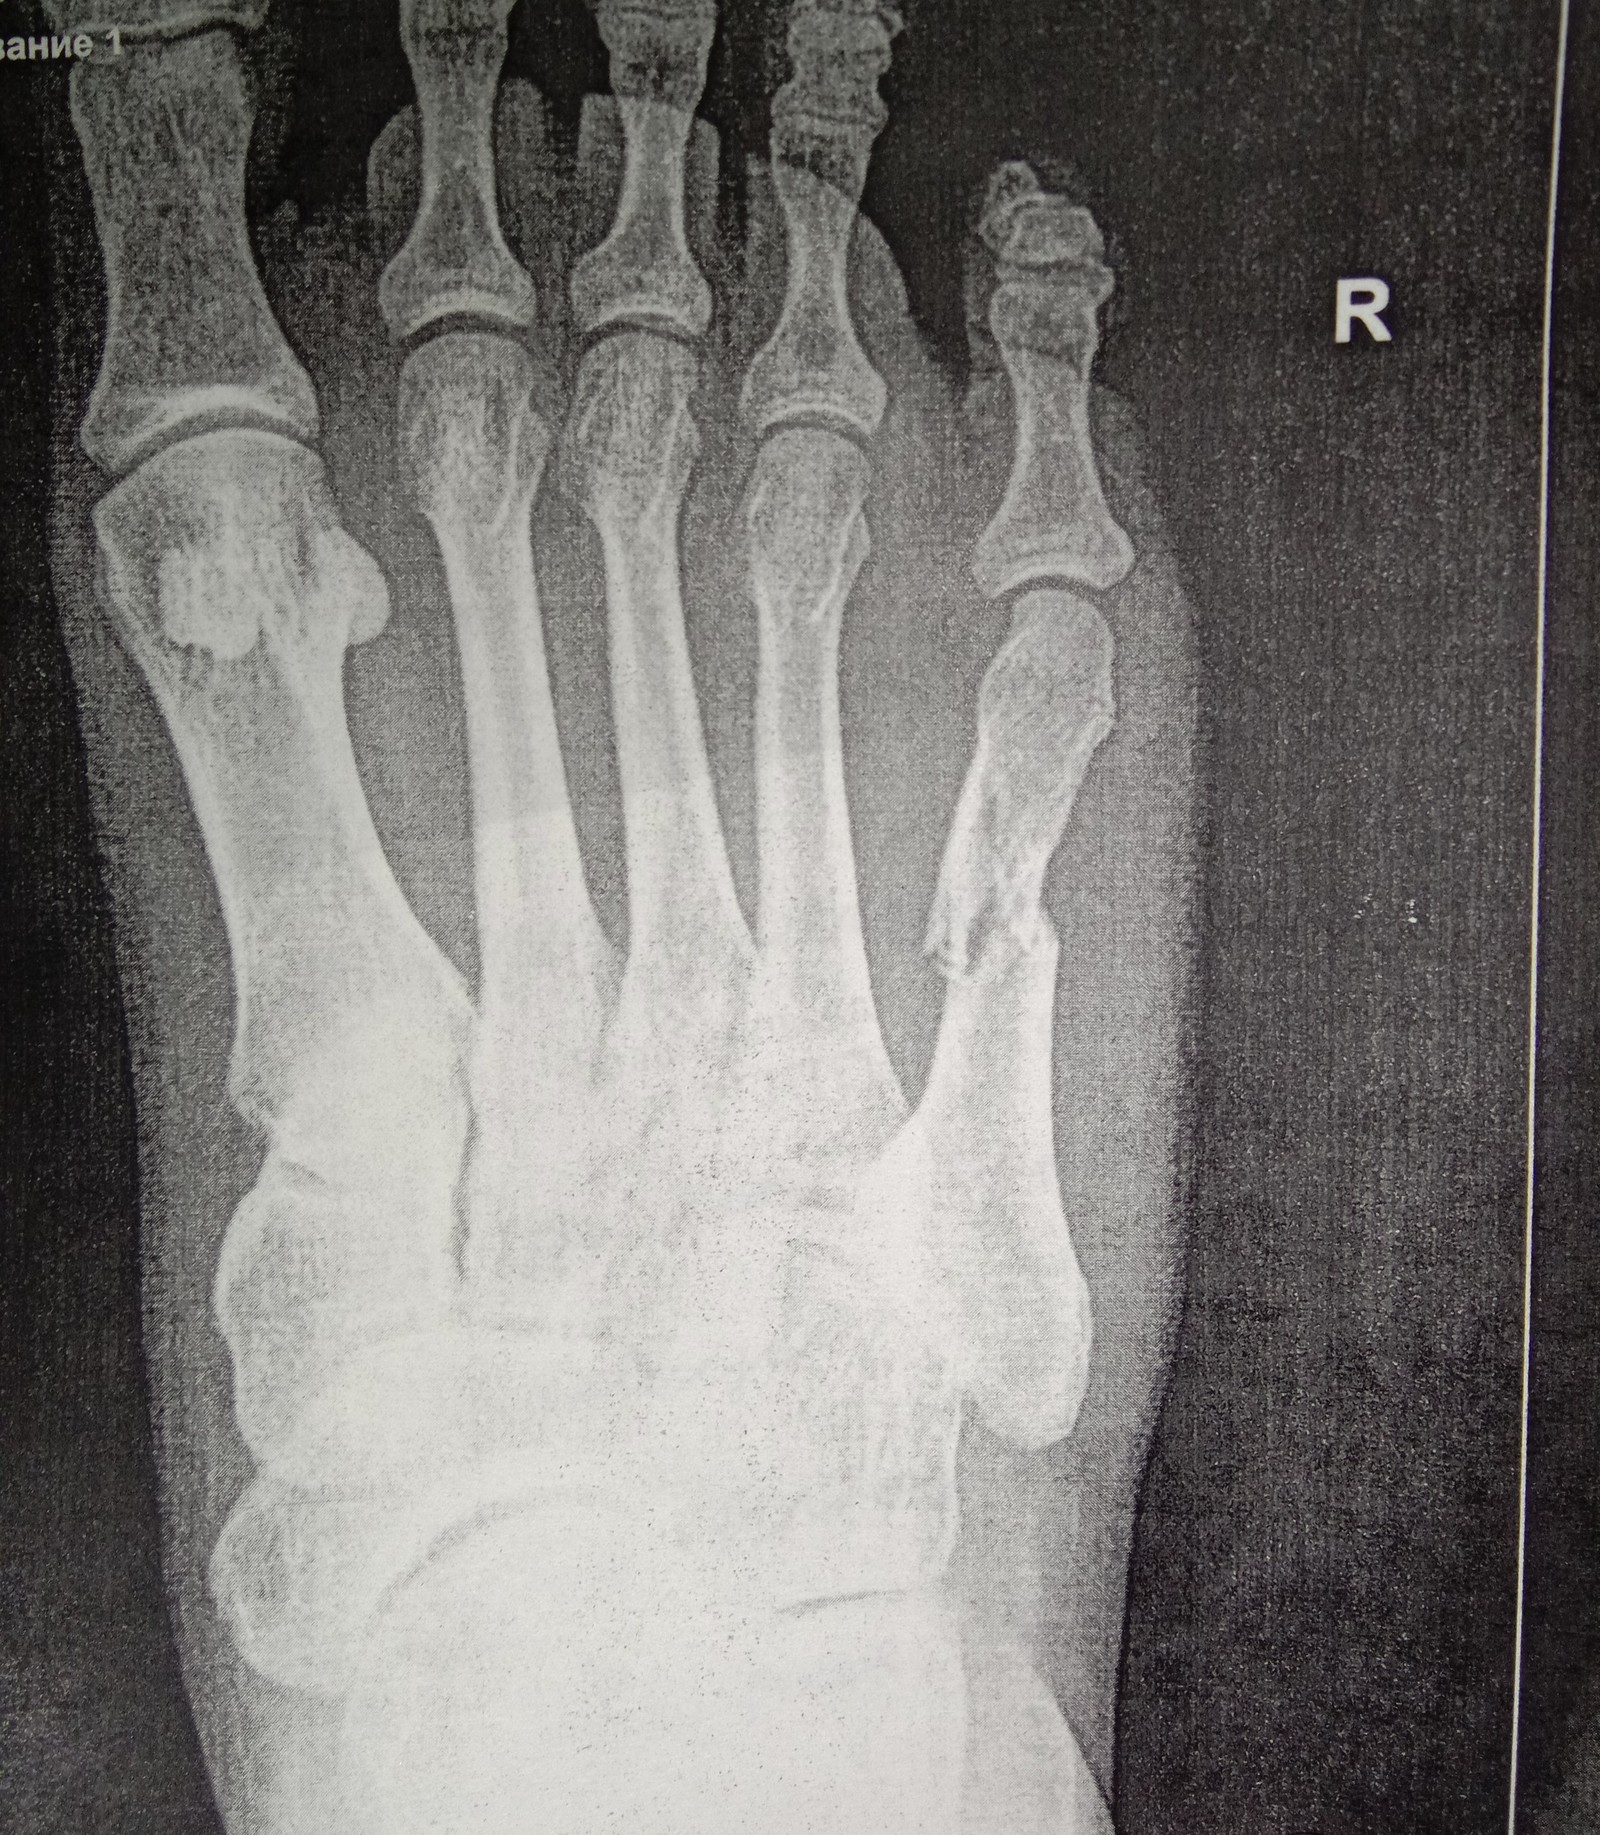

Приехали, взяли талон и направились к травматологу. В кабинете врач осмотрев ногу, направил меня на рентген. И вот увидев снимок, мои опасения подтвердились.

Принесла снимки врачу, он говорит, надо вправлять ,перелом со смещением. Отправляет меня в процедурную (или как там правильно называется), я попросила врача, чтоб дедушка пошел со мной, мол с родней не страшно будет. Вот сидим с дедом смеемся над всей ситуацией, фоткаем друг друга,мол на память. И тут заходит врач, садится ко мне на кушетку и начинает протирать ногу спиртом. И тут начинается кино)) Мне становится дурно и я прошу просто полежать. Все, темнота. Очнулась когда меня уже посадили, вся мокрая и бледная. Вокруг меня бегают несколько врачей, измеряют давление ,смотрят зрачки, а я вроде и пришла в себя, но ничего понять не могу.

Понедельник, мы с мужем в приемном покое встречаем врача. Объясняем ему все , он отправляет нас на рентген. Но увы и ах, кость встала ровнее, но "домик"остался. Идем в процедурную, там мне вправляют кость, делают гипс и опять на рентген. Нога встала чуть ровнее, но может "соскочить " в любой момент. В общем надо вставлять спицу.